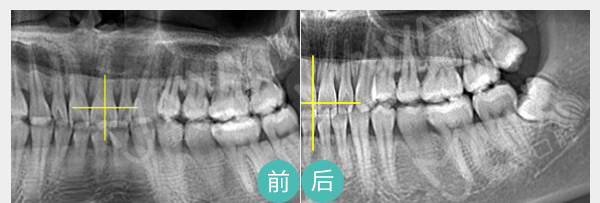

麦芽树脂补牙即用无菌器械清除龋坏部分,清洗窝洞后用树脂材料进行填充,以恢复其外形和功能,对于严重的龋齿,需要进行根管治疗。

适应症:龋齿引起口臭